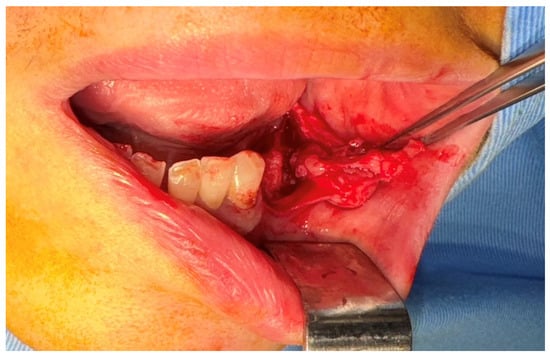

2.2. First Surgical Intervention

2.4. Second Surgical Intervention

2.5. Third Surgical Intervention